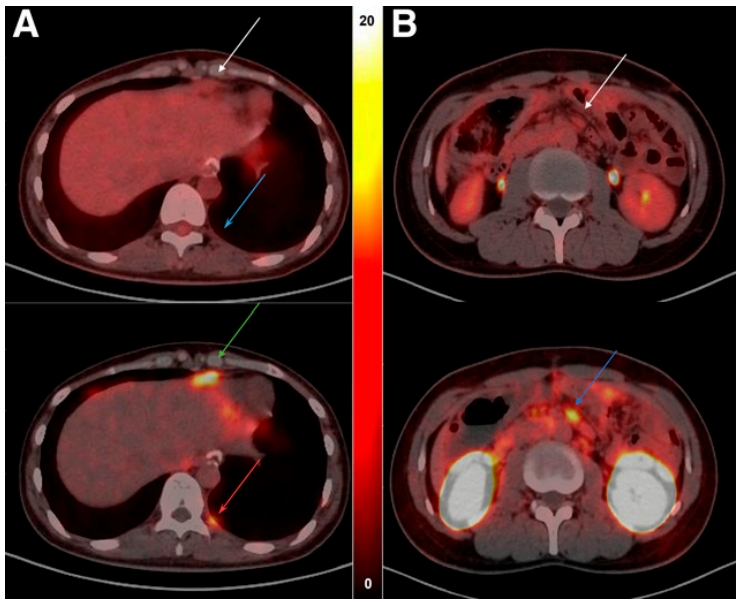

68Ga-NC-BCH和18F-FDG兩種方法檢測到的所有陽性病灶的腫瘤-非腫瘤(T/NT)比率存在顯著差異。亞組分析顯示,68Ga-NC-BCH PET/CT檢測到的淋巴結(jié)和腹膜轉(zhuǎn)移的T/NT比率顯著高于18F-FDG PET/CT。例如,患者9(晚期胃癌,女性)左側(cè)胸膜轉(zhuǎn)移結(jié)節(jié)和增厚的腹膜在18F-FDG PET/CT上未顯示明顯攝取,而在68Ga-NC-BCH PET/CT上顯示高攝取。另外,患者4(結(jié)腸癌,男性)其腹部轉(zhuǎn)移淋巴結(jié)在18F-FDG PET/CT上顯示輕微攝取,而在68Ga-NC-BCH PET/CT上顯示高攝取。淋巴結(jié)和腹膜是晚期胃癌的最常見轉(zhuǎn)移部位。由68Ga-NC-BCH PET/CT檢測到的病變的T/NT比例顯著較高,這種高比例更有利于病變的檢測。

圖6. (A) 患者9女性晚期胃癌,CLDN18.2表達(dá)水平為40%,2+。左側(cè)胸膜轉(zhuǎn)移結(jié)節(jié)(藍(lán)色箭頭)和增厚腹膜(白色箭頭)在18F-FDG PET/CT上未顯示明顯攝取,而在68Ga-NC-BCH PET/CT上顯示高攝取(SUVmax分別為3.1 [紅色箭頭] 和5.7 [綠色箭頭])。

(B) 患者4結(jié)腸癌,其CLDN18.2表達(dá)水平為40%,3+。在18F-FDG PET/CT上,腹部轉(zhuǎn)移淋巴結(jié)(白色箭頭)顯示輕度攝取SUVmax, 1.4,而在68Ga-NC-BCH PET/CT上同一淋巴結(jié)(藍(lán)色箭頭)顯示高攝取SUVmax,5.6。